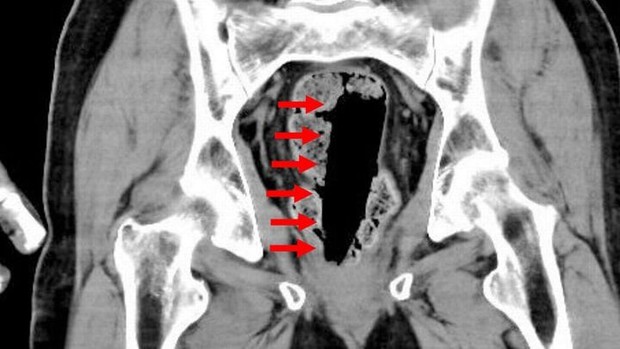

Việc chữa táo bón bằng cách nhét dị vật vào cơ thể đã gây ra những hậu quả khó lường cho những người thực hiện. Một người đàn ông ở Nhật Bản đã phải nhập viện sau khi nhét một lọ keo hình trụ vào trực tràng với hy vọng chữa táo bón. Kết quả chụp CT cho thấy hộp keo kích thước lớn vẫn còn nguyên chất keo lỏng bên trong, khiến bác sỹ phải thực hiện ca phẫu thuật khẩn cấp. Điều này làm người đàn ông này phải trải qua những giây phút ác mộng trong bồn tắm, cũng như khi nhập viện với tình trạng bất tỉnh.